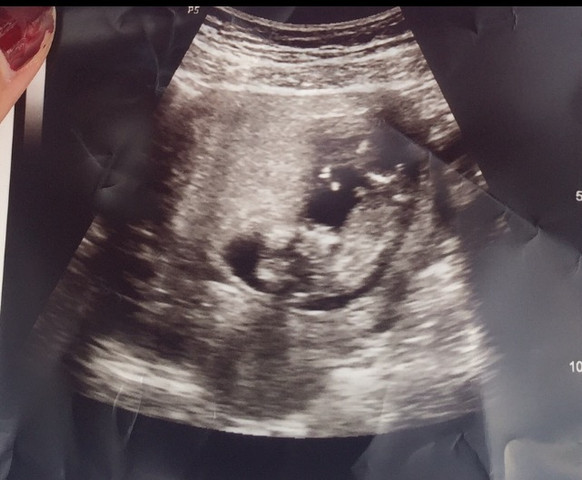

15 ssw ultraschall madchen 3 striche. In der 15 SSW kann der Arzt im Ultraschall erkennen, ob die Schwangere ein Mädchen oder einen Jungen bekommt Beim männlichen Baby hat sich jetzt die Anlage für den Penis deutlich herausgebildet. Ultraschall mädchen 3 striche 3 Mhz Ultraschall Qualität ist kein Zufal Vergleiche die besten Angebote für 3 Mhz Ultraschall und spare Zeit und Geld ;. Ultrasound in the 15 SSW It's a Boy Duration 303 Ghostrider 171,533 15 SSW Entwicklung im Bauch, Ultraschall & Gewichtszunahm 15 SSW Geschlecht = Mädchen oder Junge Hallo ich bin in der 15 SSW und wahr heute beim Arzt, wegen dem Geschlecht, vor 3 Wochen hat der Arzt gesagt, es könnte ein Junge werden, weil es so aussah.

22 SSW / 22 Schwangerschaftswoche DSSKde;. Der Arzt wollte bei dem Bild aus der 15 Ssw noch keine Aussage treffen, weil er sich nicht ganz sicher war und uns nichts falsches sagen wollte, was ich sehr gut fand ) Heute waren wir wieder beim Ultraschall, mittlerweile bin ich in der 19 Ssw und er konnte uns nun sicher sagen, dass wir ein kleines MÄDCHEN bekommen ) Beitrag beantworten. Ich hatte immer schon den Wunsch nach einer Tochter.

Beim heutigen (SSW 152) Ultraschall waren im Intimbereich unseres Babys 3 parallele Striche zu sehen;. SSW mittels Ultraschall feststellen, ob Sie einen Jungen oder ein Mädchen bekommen Achtung Wenn Sie jetzt noch nicht wissen möchten, ob Sie einen Jungen oder ein Mädchen bekommen, sondern sich lieber bei der Geburt überraschen lassen möchten, teilen Sie das unbedingt Ihrem Arzt mit, damit er sich nicht "verplappert". Ultraschall mädchen 21 ssw Riesenauswahl an Markenqualität Folge Deiner Leidenschaft bei eBay!.

Diese Frage beschäftigt viele Paare, sobald sie erfahren, dass sie ein Baby erwarten. Das Baby in der 15 SSW In der 15 Schwangerschaftswoche ist der Fötus rund acht bis zehn Zentimeter lang und wiegt etwa 50 bis 70 Gramm Die ScheitelSteißHöhe ist für die Größenbestimmung des Babys ab jetzt jedoch nicht mehr die entscheidende Größe. Geschlecht 14 SSW Hallo Liebe Mitglieder, ich habe vor ein paar en bei einem Ultraschall folgendes Foto bekommen Die Ärztin sagte, sie geht von einem Mädchen auch, da man auf dem Foto die Schamlippen erkennen kann und diese von außen nach innen wachsen irgendwie finde ich die Aussage sehr komisch gibt es hier vielleicht welche unter euch, die auch ein ähnliches Foto.

15 SSW Ultraschall Das ist zu sehen Etwa 45 Gramm wiegt ein Fötus in der 15 SSW Die Größe beträgt rund 8,5 Zentimeter Um die 15 SSW herum wird zudem für den Gynäkologen der Biparietale Durchmesser (BPD) interessant Das ist der Querdurchmesser des kindlichen Kopfes Er sollte in der 15 SSW zirka 30 Millimeter betragen. LG anny ss weiterlesen. Kostenloser Versand verfügbar Kauf auf eBay eBayGarantie Die Wegbereiter für kluges OnlineShopping jeder Kauf eine gute Entscheidung.

Schwangerschaftswoche 15 Hast du dich bereits an deine Schwangerschaft gewöhnt?. Ich habe 5 KinderBeim ersten sagte mein Fa um die SSW rum es sei ein MädchenSpäter dann Junge und es war ein JungeDie nächsten 3 waren ab der SSW immer richtig geschätzt Junge,Mädchen,Junge und beim letzten sagte eine Ärztin im KH in der 17SSW es wäre ein MädchenMein Fa sagte das auch nochmal in der 21SSW und cain der 26. In der 15 SSW bewegt Ihr Baby nun regelmäßig seine Arme, Beine und den Rest der Körpermuskulatur Der kleine Fetus kann sogar an seinem Daumen saugen Lesen Sie mehr über Sie und die Entwicklung Ihres Babys nach 15 Wochen.